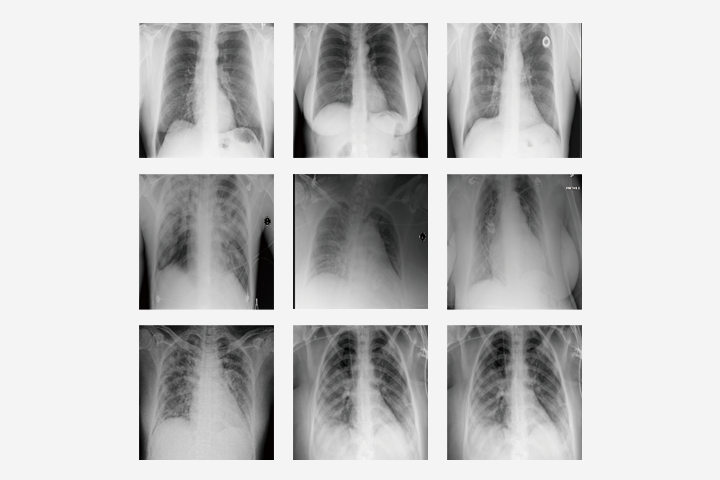

- 医療画像診断AIの脆弱性を分析・改善するアルゴリズムを開発し、COVID-19診断支援AIの安全性を向上させる